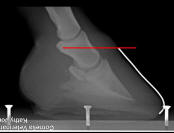

Miserably

lame Quarter Horse. P3 is penetrating the sole, with extensive sub-solar

abscessing. |

At 6

months, still room for improvement, but completely sound. |

We eliminated the sweet feed,

switched the horse to a mixed grass hay diet, but turnout on rich grass,

with a grazing muzzle was permitted. Although the horse is now

completely comfortable, a bit of separation persists, indicating the

diet is still not quite strict enough. "You can't just trim your way out

of a founder."

After these radiographs were

taken, he was moved to a new home with no grass and lots of work to do.

He is now living in a heard, happily giving riding lessons and

comfortably working as a trail horse. I will do another set of

radiographs in 6 more months and expect this improved environment to

forge a perfect hoof.